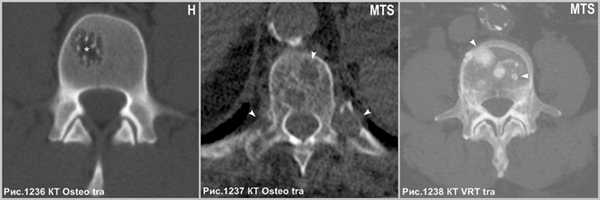

На КТ дифференциальный диагноз между метастазом и гемангиомой не представляет сложности в связи с тем, что литический метастаз выглядит в виде округлого участка без чётких контуров, вызывая рассасывание губчатой и компактной костной ткани (головки стрелок на рис.1237), а склеротический метастаз в виде очагов уплотнения костной ткани посреди губчатого вещества тела позвонка (головки стрелки на рис.1238). Гемангиома имеет уплотнённые вертикальные костные балки на фоне разряженной структуры губчатого вещества тела позвонка (звёздочка на рис.1236).